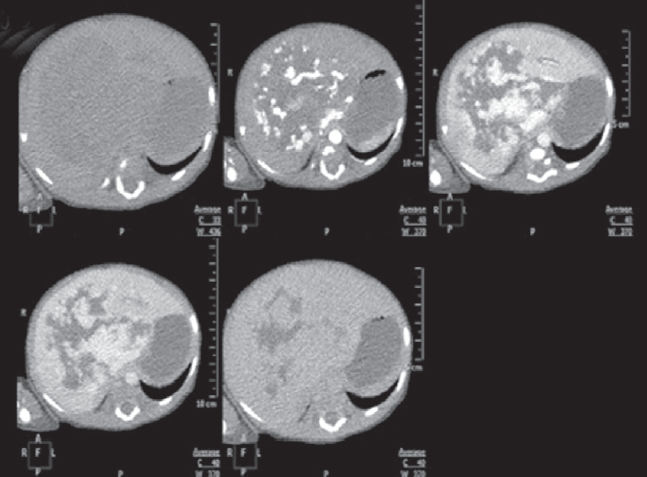

Гемангиомы — наиболее часто встречающиеся доброкачественные сосудистые образования печени детского возраста, которые могут приобретать как злокачественное течение, так и спонтанно регрессировать. На первом году жизни их распространенность составляет 10–12 %. Среди недоношенных детей распространенность гемангиом коррелирует со степенью недоношенности. Гемангиомы небольших размеров, как правило, не требуют специфического лечения и протекают бессимптомно. Образования крупных размеров могут вызывать жизнеугрожающие состояния: тяжелую тромбоцитопению с коагулопатией (синдром Казабаха – Меррита), анемию, кровоизлияние в опухоль, спонтанные и травматические разрывы опухоли, сердечную недостаточность, связанную с внутриопухолевым шунтированием кровотока, синдром абдоминальной компрессии, тяжелый гипотиреоз. Диагноз устанавливается на основании совокупности данных медицинской визуализации, лабораторной диагностики и клинической картины. В данном обзоре представлены ключевые моменты общей классификации, наиболее характерные диагностические признаки, а также базовые алгоритмы лечения гемангиом печени у новорожденных и детей первого года жизни. Также описаны 2 клинических случая новорожденных с гигантскими гемангиомами печени, которые обследовались и получали лечение в отделении патологии новорожденных и детей грудного возраста Перинатального центра Санкт-Петербургского государственного педиатрического медицинского университета с описанием особенностей течения каждого из них.